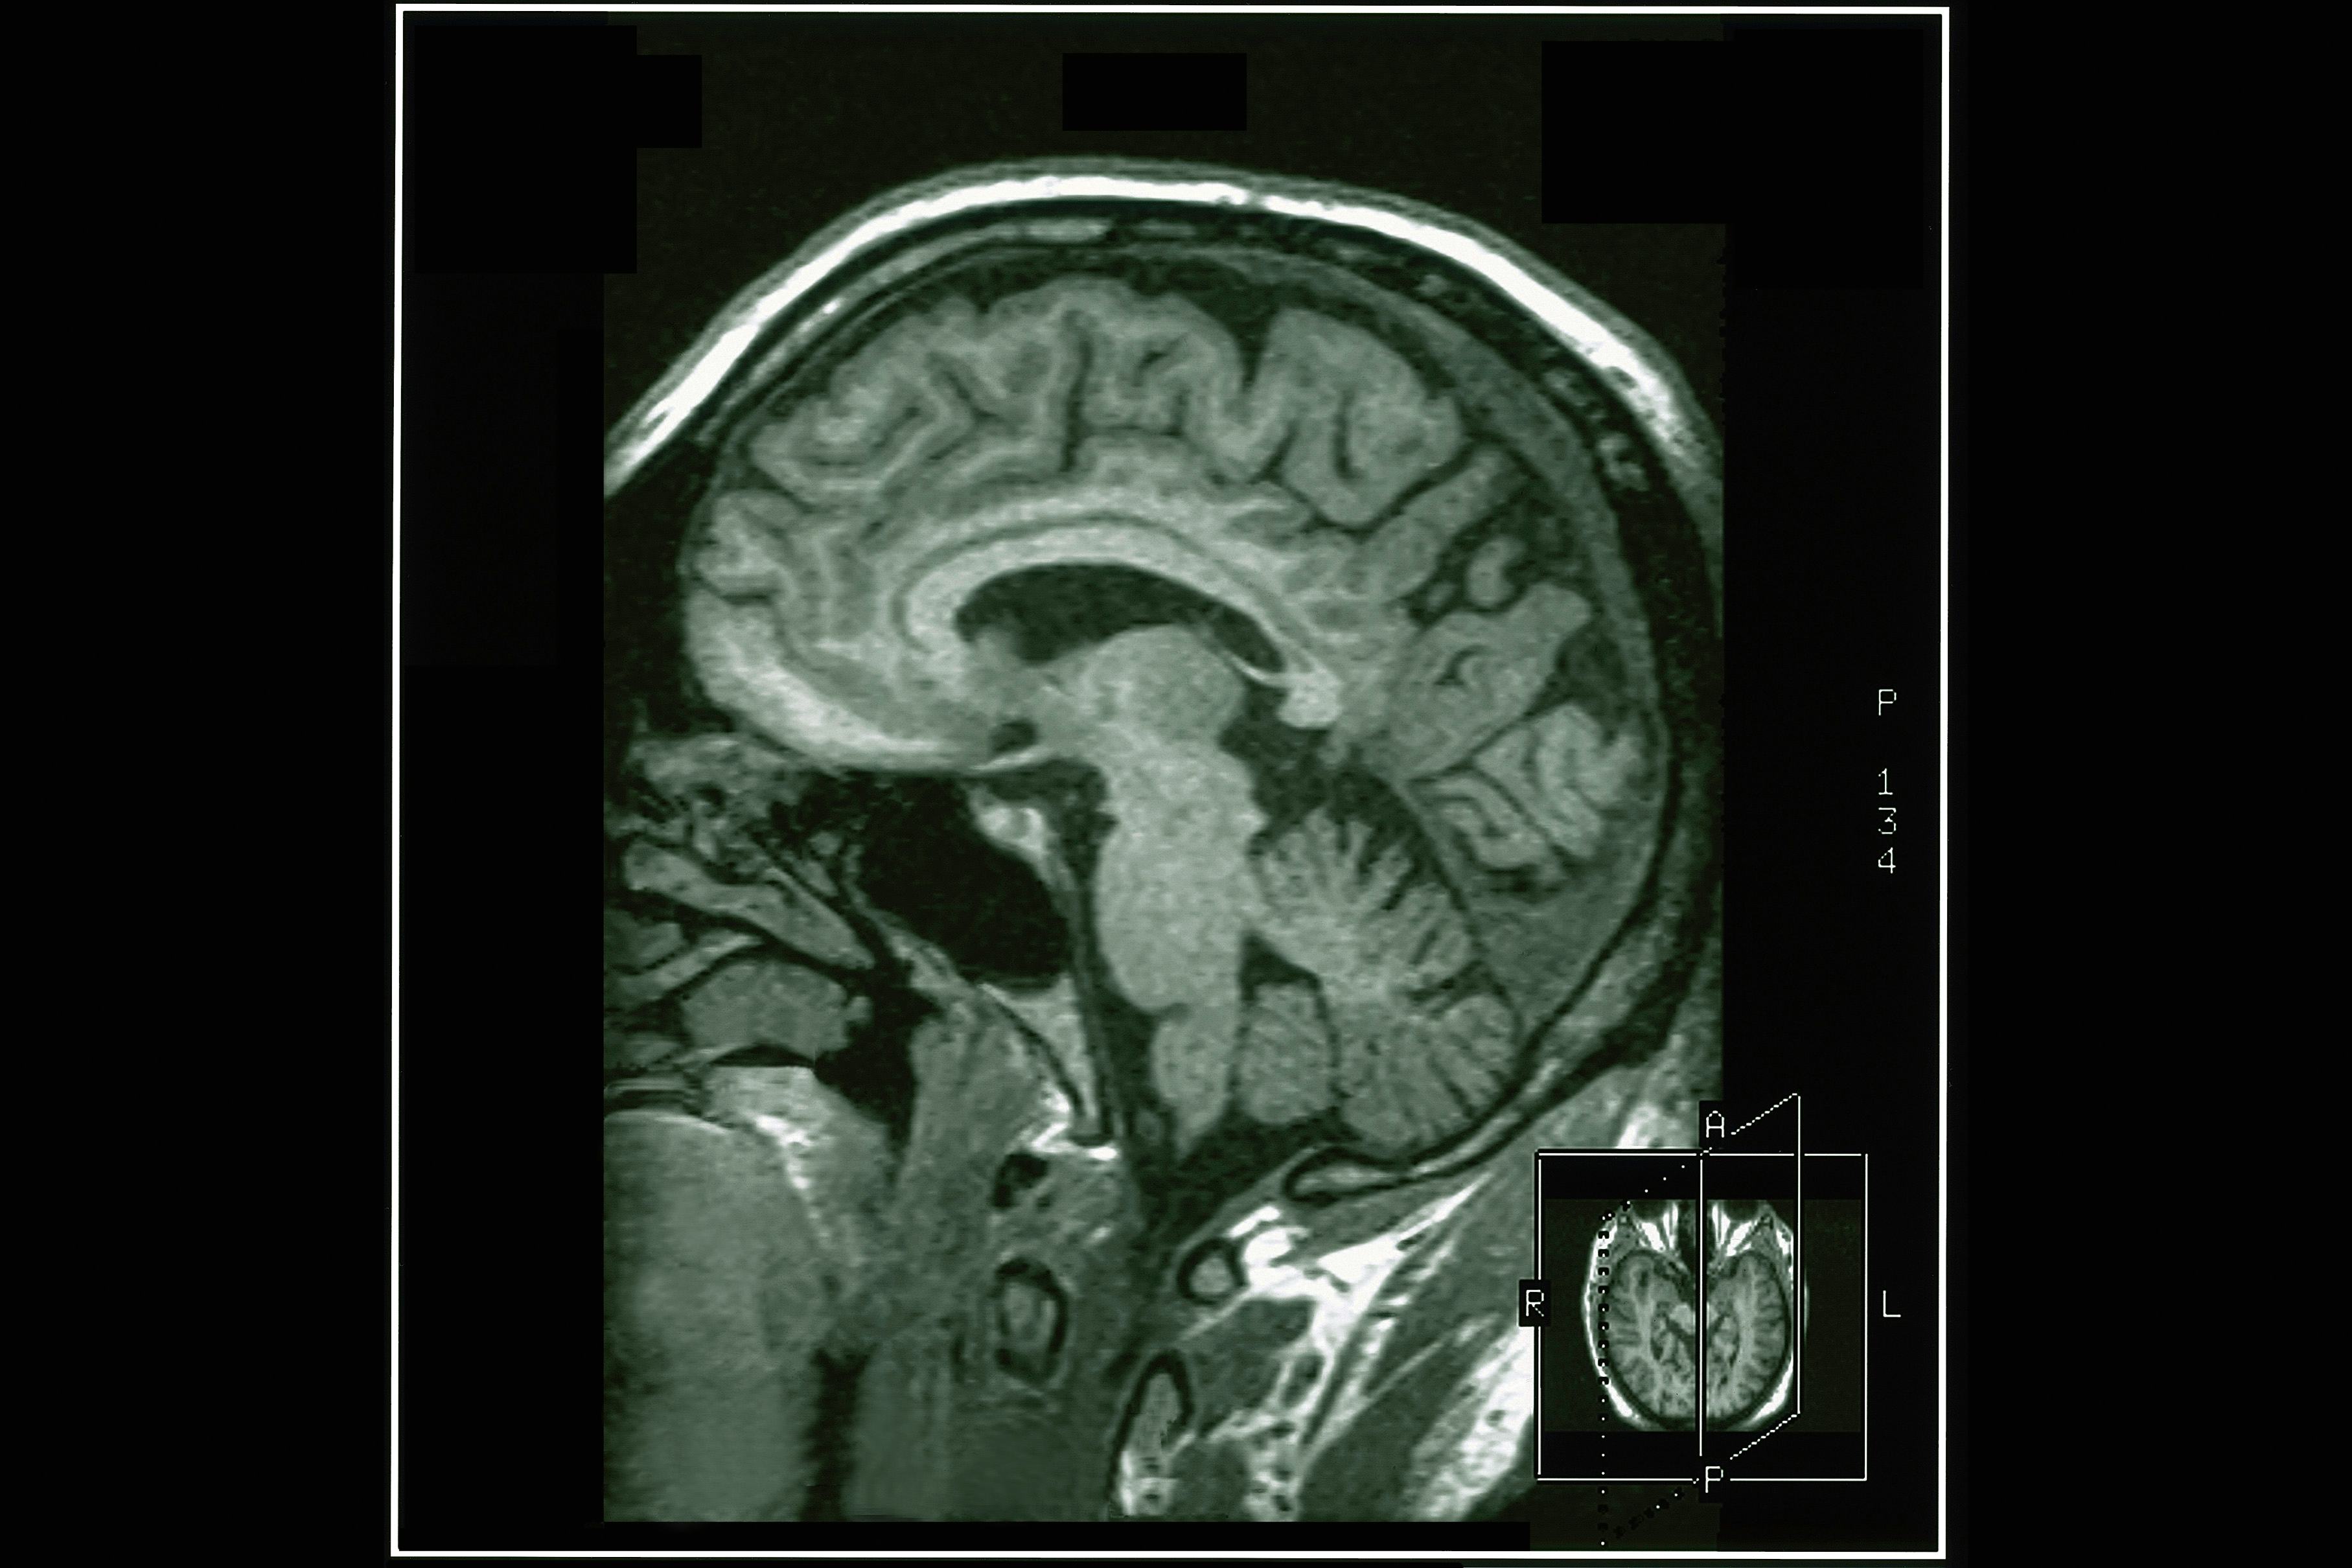

“Sexual function is a critical part of who we are as a genome,” Mills tells Inverse. “That’s how we reproduce, so it’s hardwired not only in our prefrontal cortex, which is the part of our brain involved in decision making, but also deeper into our thalamus and hypothalamus.”

The thalamus and hypothalamus are part of the limbic system, affectionately known as the “lizard brain.” The limbic system controls six very important Fs: fight, flight, feeding, fear, freezing up, and, you guessed it, fornication.